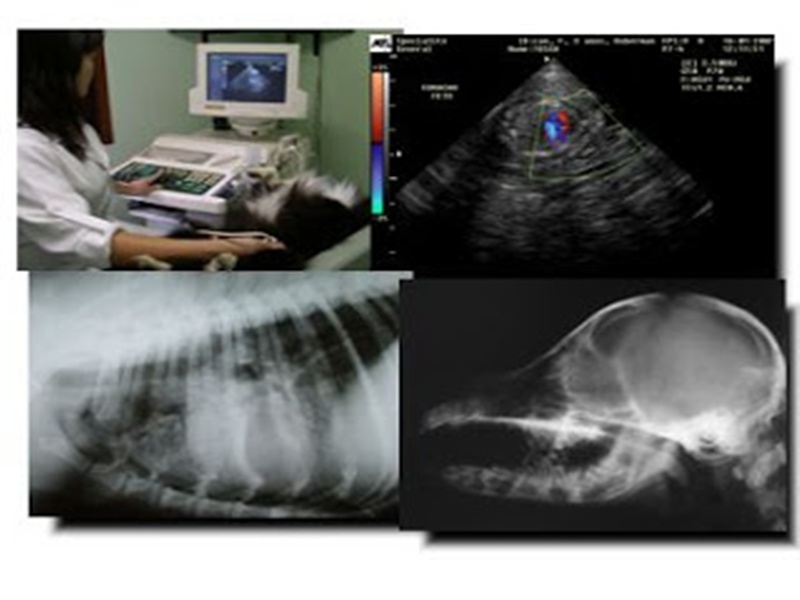

Para ampliar a oferta de serviços oferecidos pela Secretaria Municipal de Saúde à população de Cajueiro da Praia, a Prefeita Vânia Ribeiro autorizou a contratação de médico para realizar exames de ultrassom nas especialidades gestacional, pélvica, abdominal, próstata e transvaginal.

Com essa medida da Prefeita Vânia Ribeiro, a Unidade de Saúde de Cajueiro da Praia amplia os cuidados com a saúde da mulher, em virtude do crescimento da demanda no município. A saúde do homem também mereceu atenção especial, possibilitando a prevenção com o exame da próstata.

O Secretário Municipal de Saúde, Pedro Fontenele Júnior, informa que serão realizados mais de 60 atendimentos de ultrassom por mês, e que, caso seja necessário, a oferta de exames será aumentada, para que todos os moradores que precisem dos serviços em Cajueiro da Praia sejam contemplados.